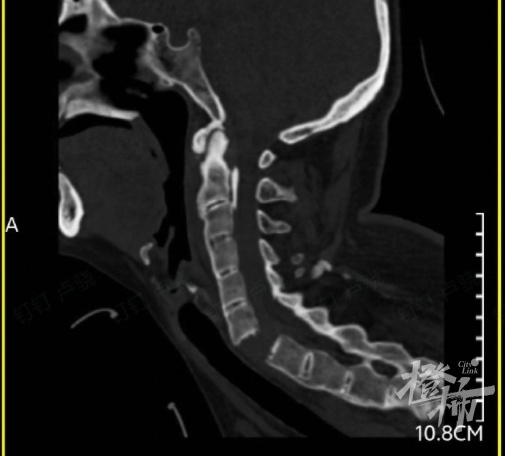

当时,刘女士出现颈部疼痛、四肢无力的症状,紧接着发现自己全身不能活动。随后,她被紧急送往附近的医院救治,通过颈椎影像检查后发现,刘女士颈椎6-7节完全断离,颈椎骨折造成脊髓损伤,导致全身瘫痪。

△检查发现,刘女士的颈椎完全断离。图源:橙柿互动